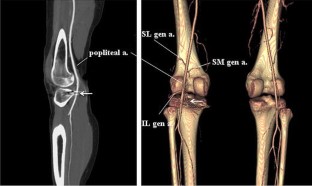

This study reports a case of unusual vascular complication related to the staple fixation for the tibial avulsion fracture of the posterior cruciate ligament (PCL). The patient, who experienced recurrent hemarthrosis 12 months after staple fixation for the avulsion fracture of the PCL, was successfully managed by removing the staple and suturing the bleeding focus of the popliteal artery. Injury to the popliteal artery by the prominent staples could be the culprit causing the recurrent hemarthrosis. This type of delayed popliteal artery injury should be kept in mind in open reduction and internal fixation for the tibial avulsion fracture of the PCL.

Fig. 1